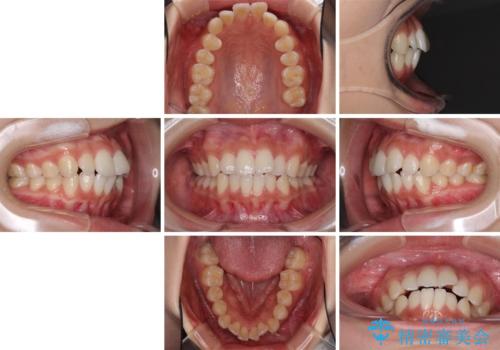

前歯のデコボコと突出感 インビザラインで改善

- 上下前歯のデコボコを気にして来院された患者様です。

インビザラインによる上下歯列の側方拡大と後方移動、IPR(歯と歯の間を削る)にるスペースの獲得により歯列を整えることとしました。

骨格的な左右差があったため、上下の正中を合わせることは困難かと思われましたが、何とか合わせることができました。

一方、骨格の差は改善できないため、奥歯の咬み合わせに物足りなさを感じました。

奥歯の咬み合わせによる不自由はなく、患者様に大変満足していただきました。